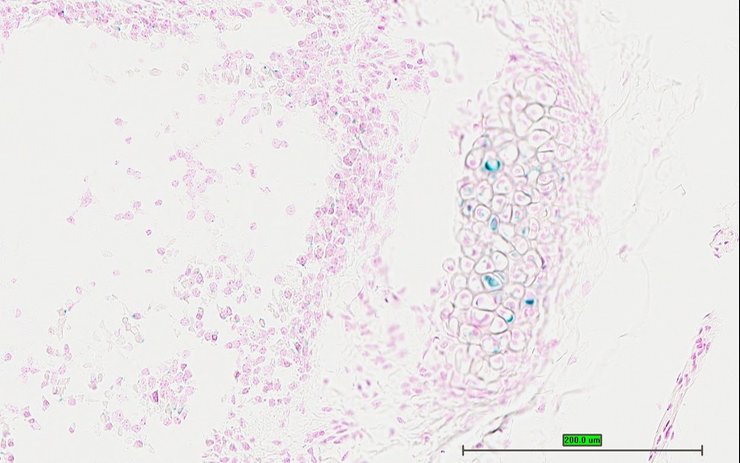

TS28: uterus Present UC Davis_1884115

Specimen UC Davis_1884116: postnatal adult; Sumo1tm1.1(KOMP)Vlcg/Sumo1+ (more )

Structure Level Pattern Image Note

TS28: uterus Present UC Davis_1884116